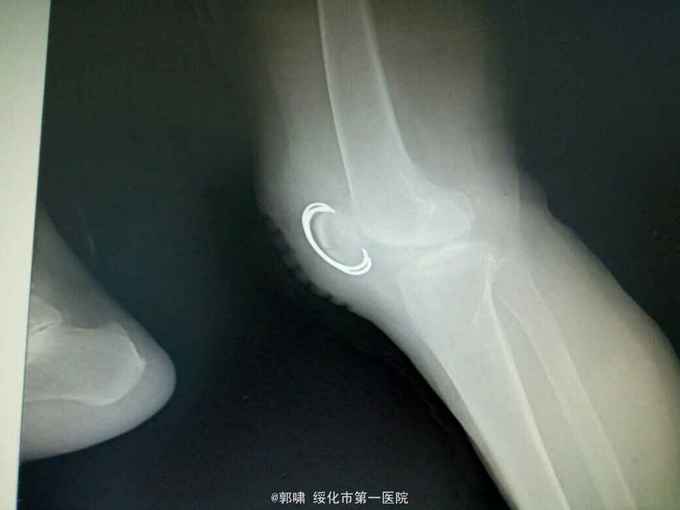

左膝关节摔伤,肿胀,畸形,活动受限一小时。收入院。患者于一小时前滑倒摔伤。当即倒地,左膝关节肿胀,畸形不能行走。门诊拍片示:左膝关节髌骨骨折,断端移位。门诊以左髌骨骨折收入院。

左膝关节肿胀,局部畸形,不能下地行走。浮髌试验阳性。拍片示:左髌骨骨折。

诊断:左髌骨骨折。立即予以腰麻下行切开复位内固定术。术中复位骨折,缝合筋膜,冰水浸泡髌骨爪约10分钟。待髌骨爪变软。选取合适大小的髌骨爪。应用记忆合金髌骨爪内固定。立即用40°温盐水热敷局部。使记忆合金加速抓紧。环抱。缝合爪齿二道,防止脱落。缝合关节囊,韧带组织。术毕。

应用记忆合金髌骨爪内固定髌骨骨折。手术时间基本在20----30分钟内都可以完成。局部损伤小。固定牢靠,确实。患者二个月就可以下地负重活动。具体手术技巧。一是髌骨爪提前用冰盐水侵泡10分钟左右。待记忆合金变软即可使用。二。固定牢靠后立即用40°温盐水热敷。使其快速抓紧。三,缝合爪齿,防脱。四如有粉碎,小的骨块可以缝合筋膜固定。有大骨块,最好环扎钢丝,或穿针固定,有时穿骨隧道钢丝捆扎。效果也不错。只要做到以上几点。安全无忧了!以下是以前做的片子。可以看一看。